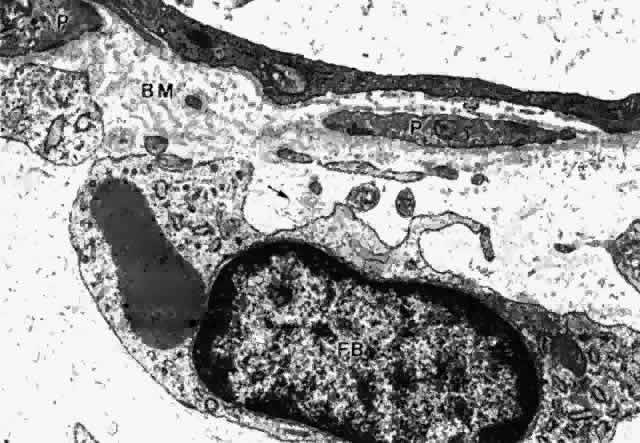

Fig. 29. Intermittent pericyte (P) coverage and lack of fenestrae in the endothelial

cell wall characterize capillaries of the deeper stroma in the pars

plicata. Basement membrane (BM) is multilayered. Fibroblast (FB) has

active rough endoplasmic reticulum and a large cisterna with granular

material. A small clump of elastic system microfibrils is seen at its

upper edge (arrow). (X 20,900) Fig. 29. Intermittent pericyte (P) coverage and lack of fenestrae in the endothelial

cell wall characterize capillaries of the deeper stroma in the pars

plicata. Basement membrane (BM) is multilayered. Fibroblast (FB) has

active rough endoplasmic reticulum and a large cisterna with granular

material. A small clump of elastic system microfibrils is seen at its

upper edge (arrow). (X 20,900)

|